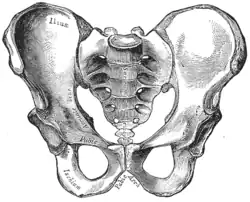

![]() Male pelvis |

![]() Female pelvis |

| Comparison between an android (left) and a gynecoid pelvis (right). | |